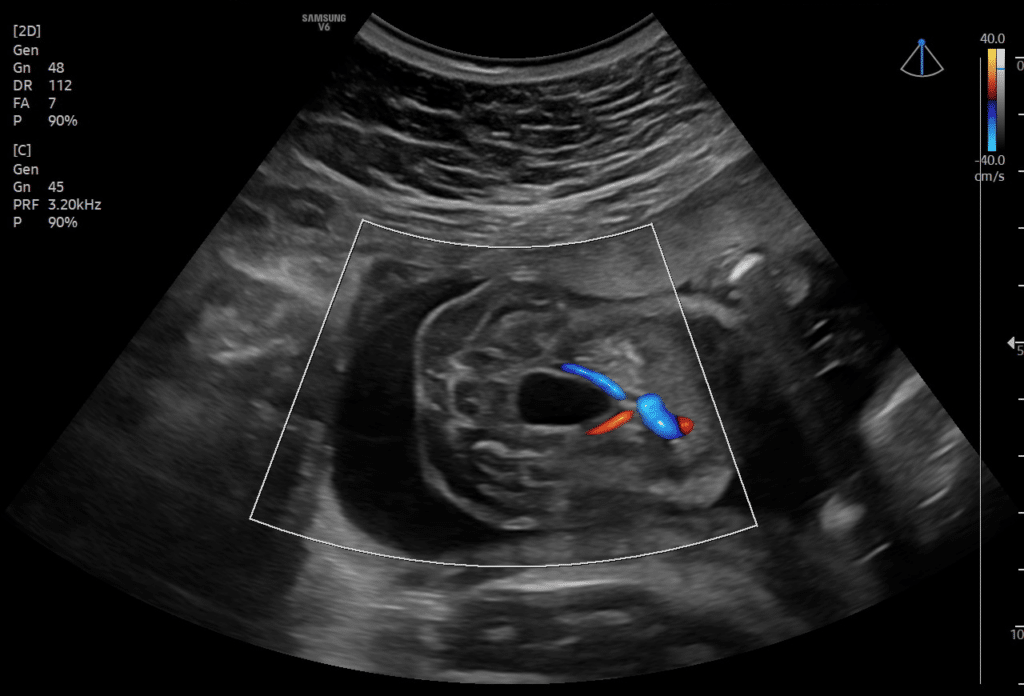

Onda de Variação de Fluxo do Ducto Venoso

Valores de Referência Para o…

Tabela de referência com os principais parâmetros dopplerfluxométricos do ducto venoso no primeiro trimestre da gestação. As tabelas aqui descritas são denominadas de tabelas de…